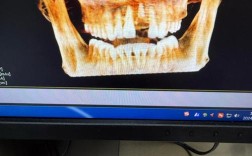

(图片来源网络,侵删)- 进口高端品牌: 如瑞士的Straumann(士卓曼)、Nobel Biocare(诺贝尔)、瑞典的Astra Tech(阿斯特拉)、德国的Ankylos(安格斯)等,这些品牌历史悠久,临床数据丰富,成功率高,技术成熟,生物相容性好,价格通常最高(单颗种植体+基台可能在 8000元 - 20000元+)。